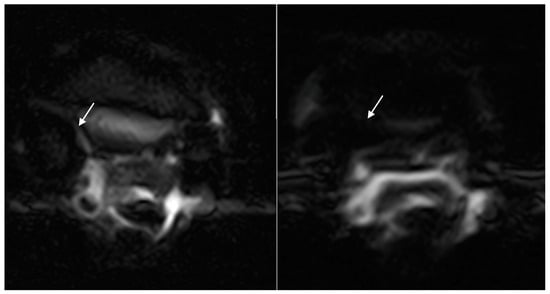

3. Results